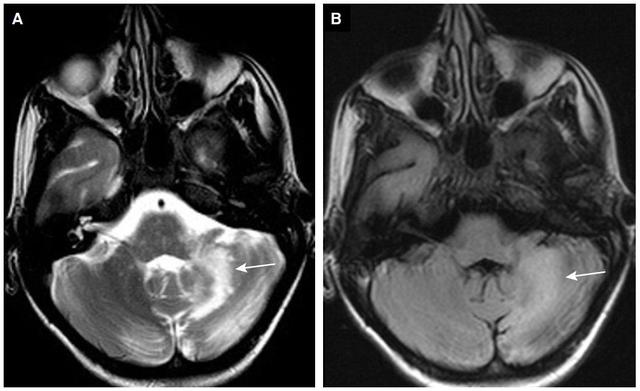

MRI可显示颈或胸脊髓后柱的高信号(图3)。对症治疗包括肌肉注射B12。维生素E缺乏通常与遗传原因有关,并且有一个类似Friedreich‘s共济失调的慢性过程。

表格总结+实战读片:掌握急性小脑性共济失调的常见病因及诊断线索丨临床必备

图3 表现为急性感觉性共济失调的维生素B12缺乏症患者。脊柱MRI T2WI显示脊髓后柱高信号。